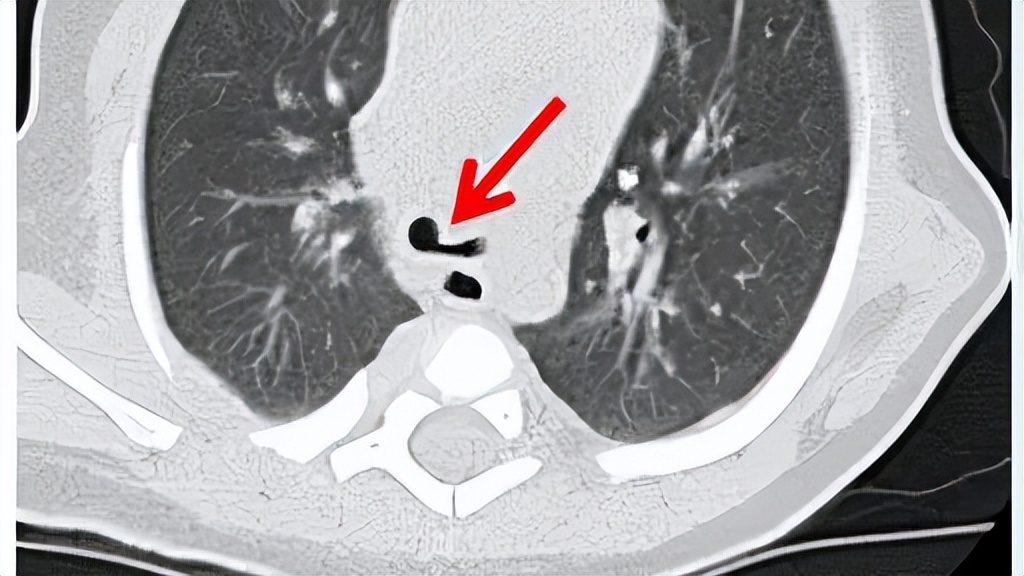

相较于X 线成像而言,多层螺旋CT应用于食管闭锁和食管气管瘘的诊断中具有一定价值,不仅能清晰显示上、下段食管及食管气管瘘,还能得到食管闭锁的两个盲端之间的距离,尤其是对于比较常见的先天性食管闭锁Ⅲa型和Ⅲb型来说很方便。

气管软化是先天性食管闭锁术后晚期并发症发生及引起死亡的重要病因。关于导致器官软化的病因,最常见原因是感染和长期呼吸机支持的高气道压力,而吞咽运动障碍、吻合口狭窄等是气管软化加剧的危险因素。为了防止气管软化的发生,建议常规行术前胸部 CT 气道重建和气管镜检查评估气道情况。